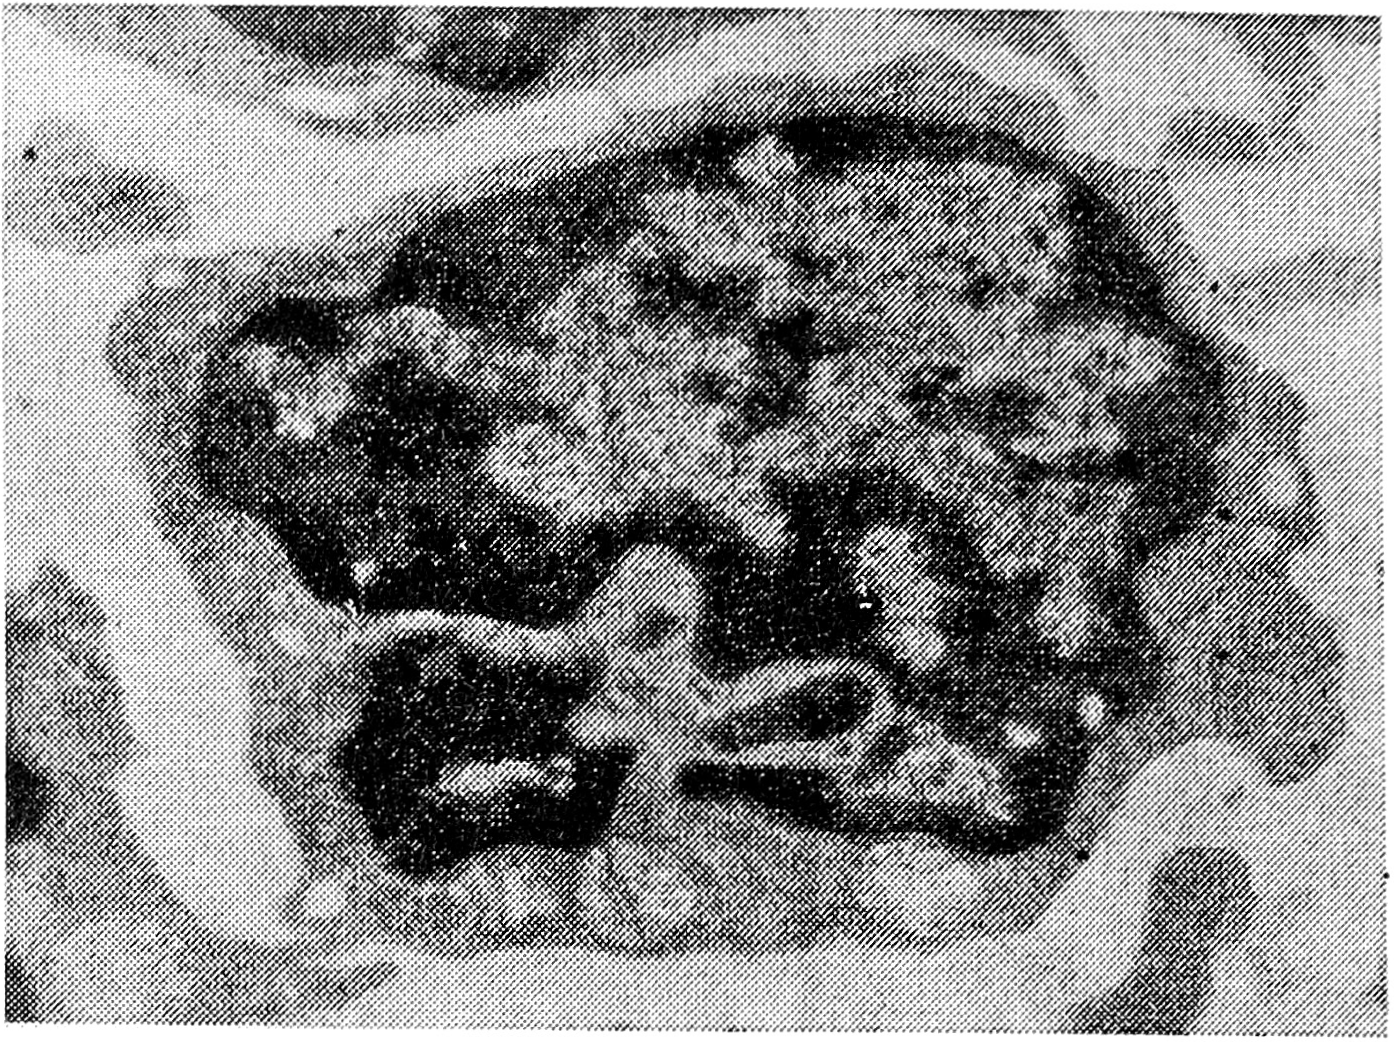

Как фиксированные, так и свободные макрофаги при помощи цитоплазматических отростков часто контактируют с лимфоцитами, ультраструктура которых также существенно меняется. Обнаруживаются так называемые активированные (иммунные, трансформированные) лимфоциты. Ядро этих клеток имеет глубокие инвагинации; диспергированный хроматин увеличен за счет плотного; в цитоплазме возрастает число рибосом, митохондрий, лизосом, вакуолей (рис. 4). Цитоплазма образует выросты, при помощи которых осуществляется контакт с другими клетками, прежде всего с макрофагами (рис. 5). Лимфоциты с такой ультраструктурой определяются как цитолитические Т-лимфоциты [10].

Рис. 4. Трансформированный (иммунный) лимфоцит. X 12000.